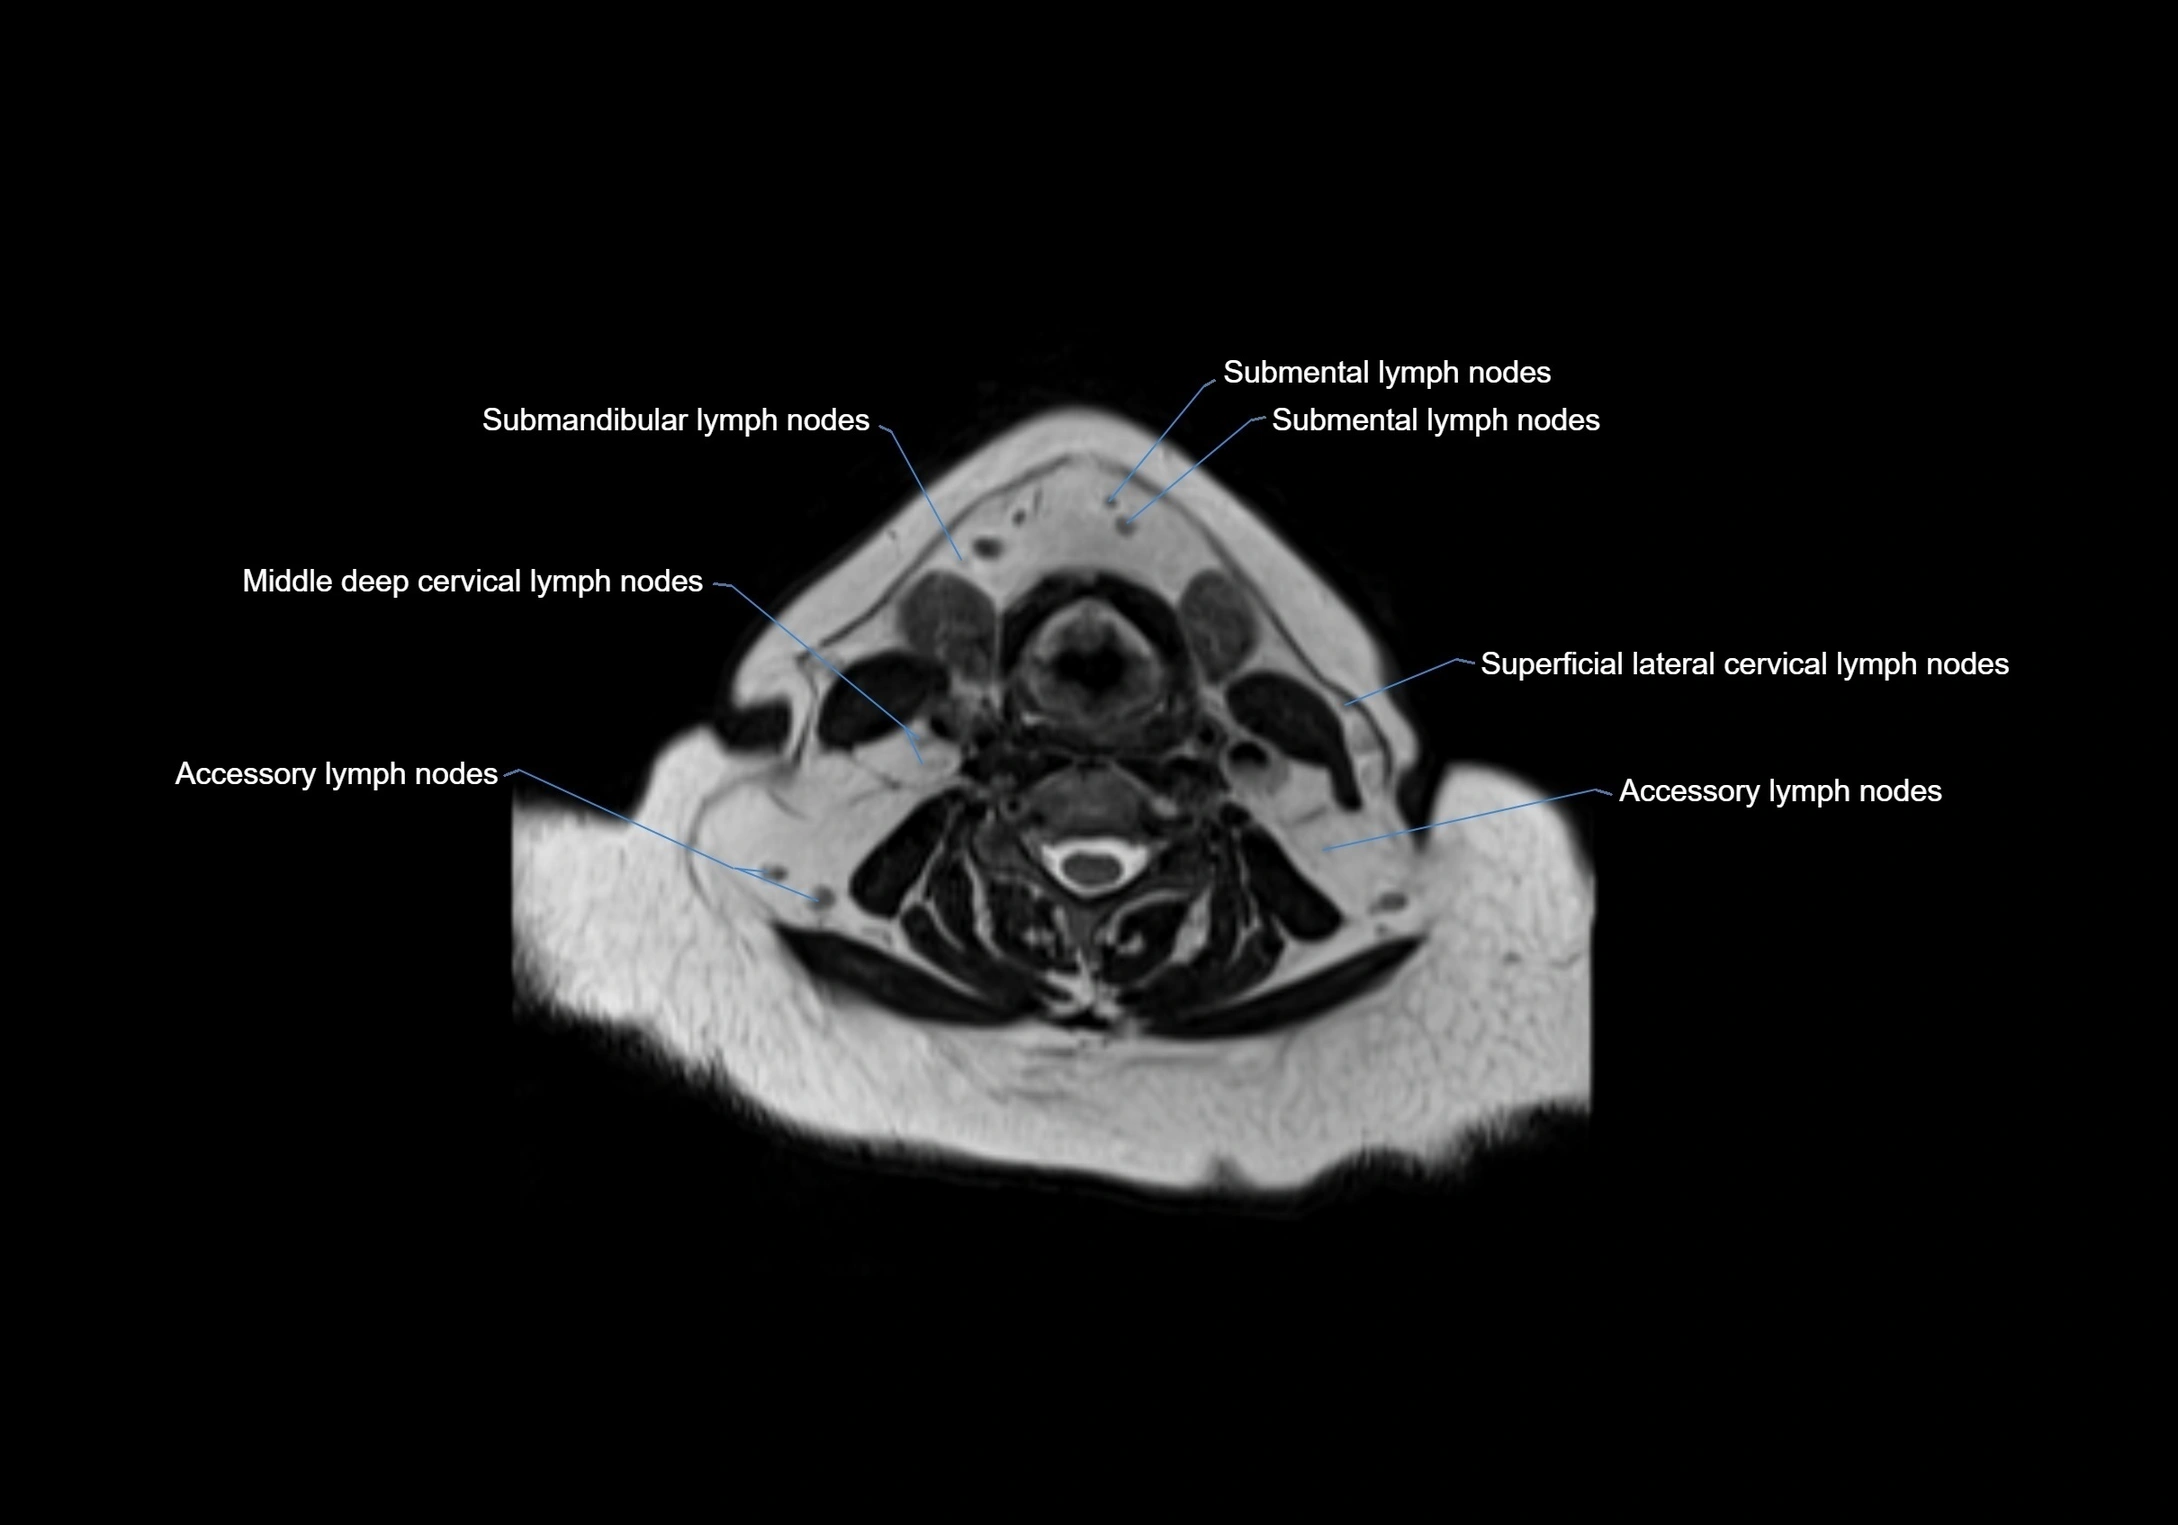

Location

• Found along primary lymph node chains, including preauricular, submandibular, parotid, and occipital regions

• Embedded in subcutaneous fat or superficial fascia, often lateral or posterior to primary nodes

• Variable in number; may occur unilaterally or bilaterally, depending on individual anatomy

MRI Appearance

T1-weighted images:

• Normal accessory nodes appear as small, oval hypointense to intermediate signal structures within subcutaneous fat

• Surrounded by hyperintense fat, enhancing contrast for visualization

• Pathological nodes may appear enlarged or rounded, sometimes with cortical thickening

MRI images

image